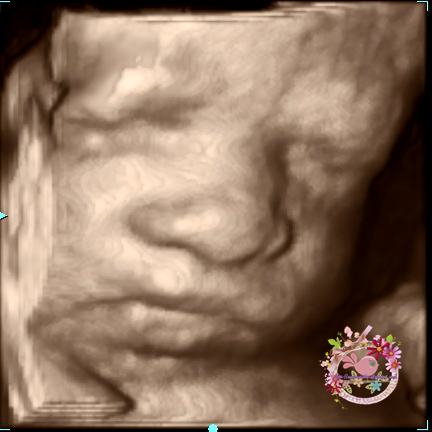

Scan 4D di Klinik Sofea for Second Time

Assalamualaikum..

Alhamdulillah da masuk 29 weeks..

Planning mmg on 28 - 30 weeks mmg nak scan 4D..

Choice mmg ke Klinik Sofea Puchong tu jer..

mmg puas hati..

setakat ni mmg rate die rendah berbanding klinik2 lain..

and one more thing x payah appointment bagai..

tp kene la tggu skt..

mmg x dinafikan klinik ni mmg tersgt2 ramai patient..

tp doc sofea tu baik..

mgkin sbb tu ramai suka dtg klinik die walaupun ramai dan queue yg panjang..

Last time pergi Klinik Sofea ni pun masa scan 4D tuk Abg Ameer..

boleh rujuk di link atas..

the best thing this time..gune panel husband jer..

x yah byr..kihkih..

oh ye yg gmbr dot dot baby yg ni pun da nmpk jolas da..

tp kite simpan jo lah..

kahkahkah..